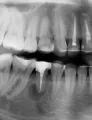

После просмотра рентгеновского снимка стоматолог сказал, что у меня киста на корне зуба, т.к. канал не до конца был запломбирован. Ближайшие к нему зубы без кисты. Врач говорит, если он Вас не тревожит, то можете пока зуб не удалять. Мне бы не хотелось удалять зуб только из-за кисты.